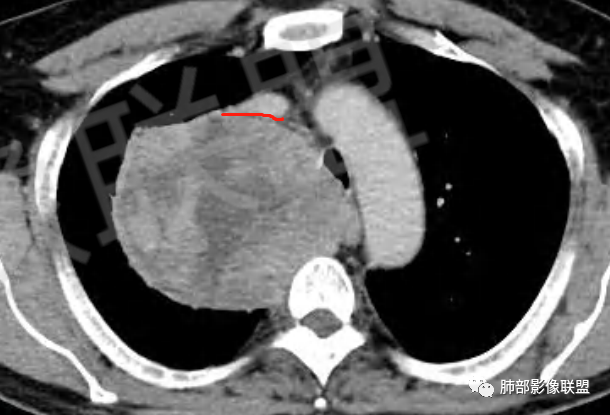

好发于肺胸壁交界区或纵隔交界区,病灶部位对病灶性质判断有较大价值。多单发,有包膜,边界清。

密度:与肿瘤细胞疏松或密集、胶原纤维含量、出血、坏死、囊变及黏液变性等有关。镜下由梭形细胞组成、细胞间由胶原纤维沉积,CT平扫肿瘤实性部分为等、稍低密度,胶原纤维易发生黏液变性或囊变,呈多发灶性或不规则星芒状低密度区,较少出现钙化。一般肿瘤小,密度多均匀,肿瘤大,多发生坏死、囊变,密度多不均匀,。

强化方式:多均匀或不均匀明显强化,增强肿瘤内可见迂曲血管影(蛇纹血管等),肿瘤较大可见“地图样”强化。